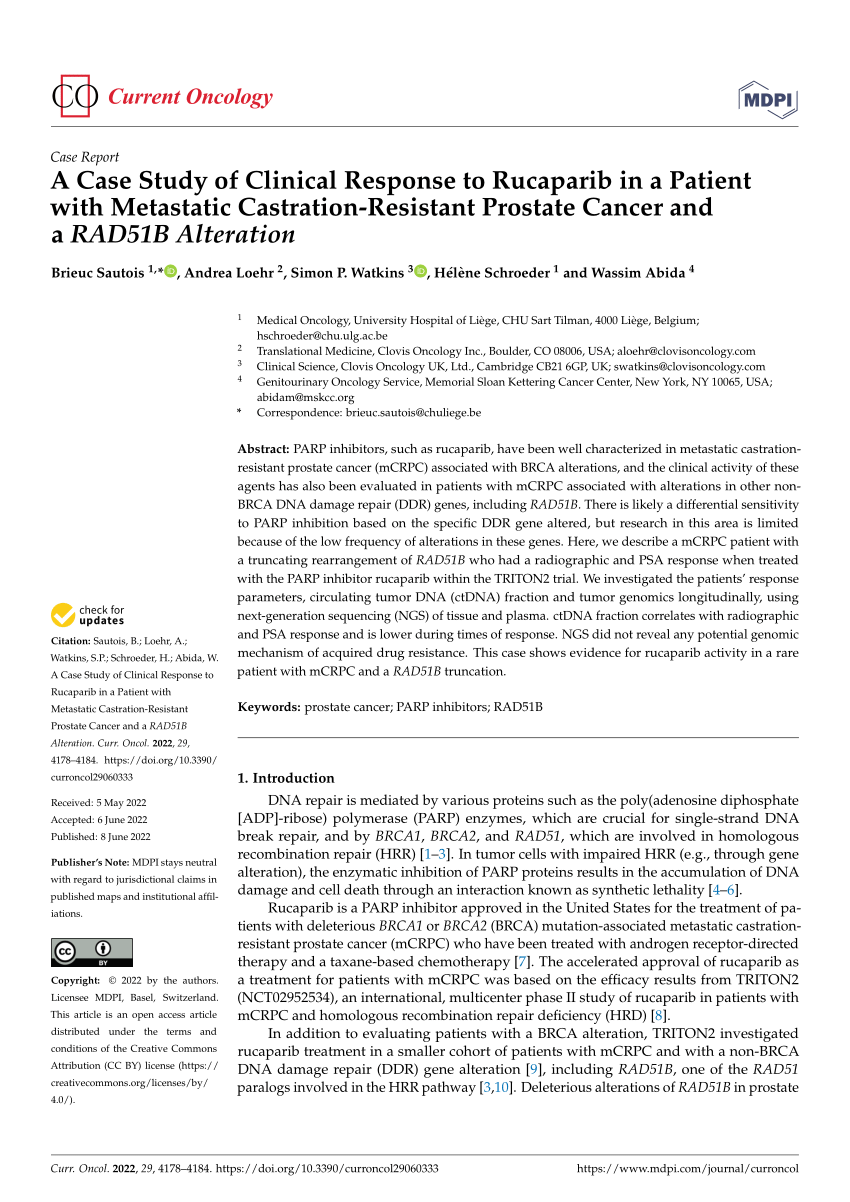

PDF) A Case Study of Clinical Response to Rucaparib in a Patient with Metastatic Castration-Resistant Prostate Cancer and a RAD51B Alteration

Rucaparib for Patients with Metastatic Castration-Resistant Prostate Cancer in the TRITON3 Trial – Oliver Sartor

Rucaparib Improves rPFS Vs Physician's Choice in BRCA+ mCRPC

ASCO GU 2023: Rucaparib for Metastatic Castration-Resistant Prostate Cancer (mCRPC): TRITON3 Interim Overall Survival and Efficacy of Rucaparib vs Docetaxel or Second-Generation Androgen Pathway Inhibitor Therapy